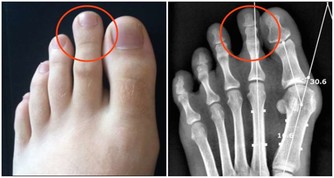

一、上下樓梯,磨損關節

杭州骨科專家、浙醫二院的戴雪松說他很少登山,因為傷膝蓋。為什麼爬樓、登山傷膝蓋呢?

從解剖學角度來分析,膝關節的周圍肌肉薄弱,上下骨骼形成的槓桿長,承受了人體86%的重量,所以膝關節在運動中最易受傷。

有一個數據:走路時髖關節、膝蓋等承受重量約是體重的1.6倍,快走是3.6倍,跑步則是5倍。

以一個體重60公斤的人為例,平路行走時兩邊膝蓋各承重60公斤,但爬樓梯或爬山時膝蓋負重竟變成高達240公斤。

上山時膝關節負重等於自身體重,而下山時除了自身體重以外,還要負擔下沖的力量,這樣的衝擊會加大對膝關節的磨損。

▲爬樓梯時,腰部以下的關節都要承受運動者自身的體重,其中以膝蓋受力最多,為平時的4倍左右。